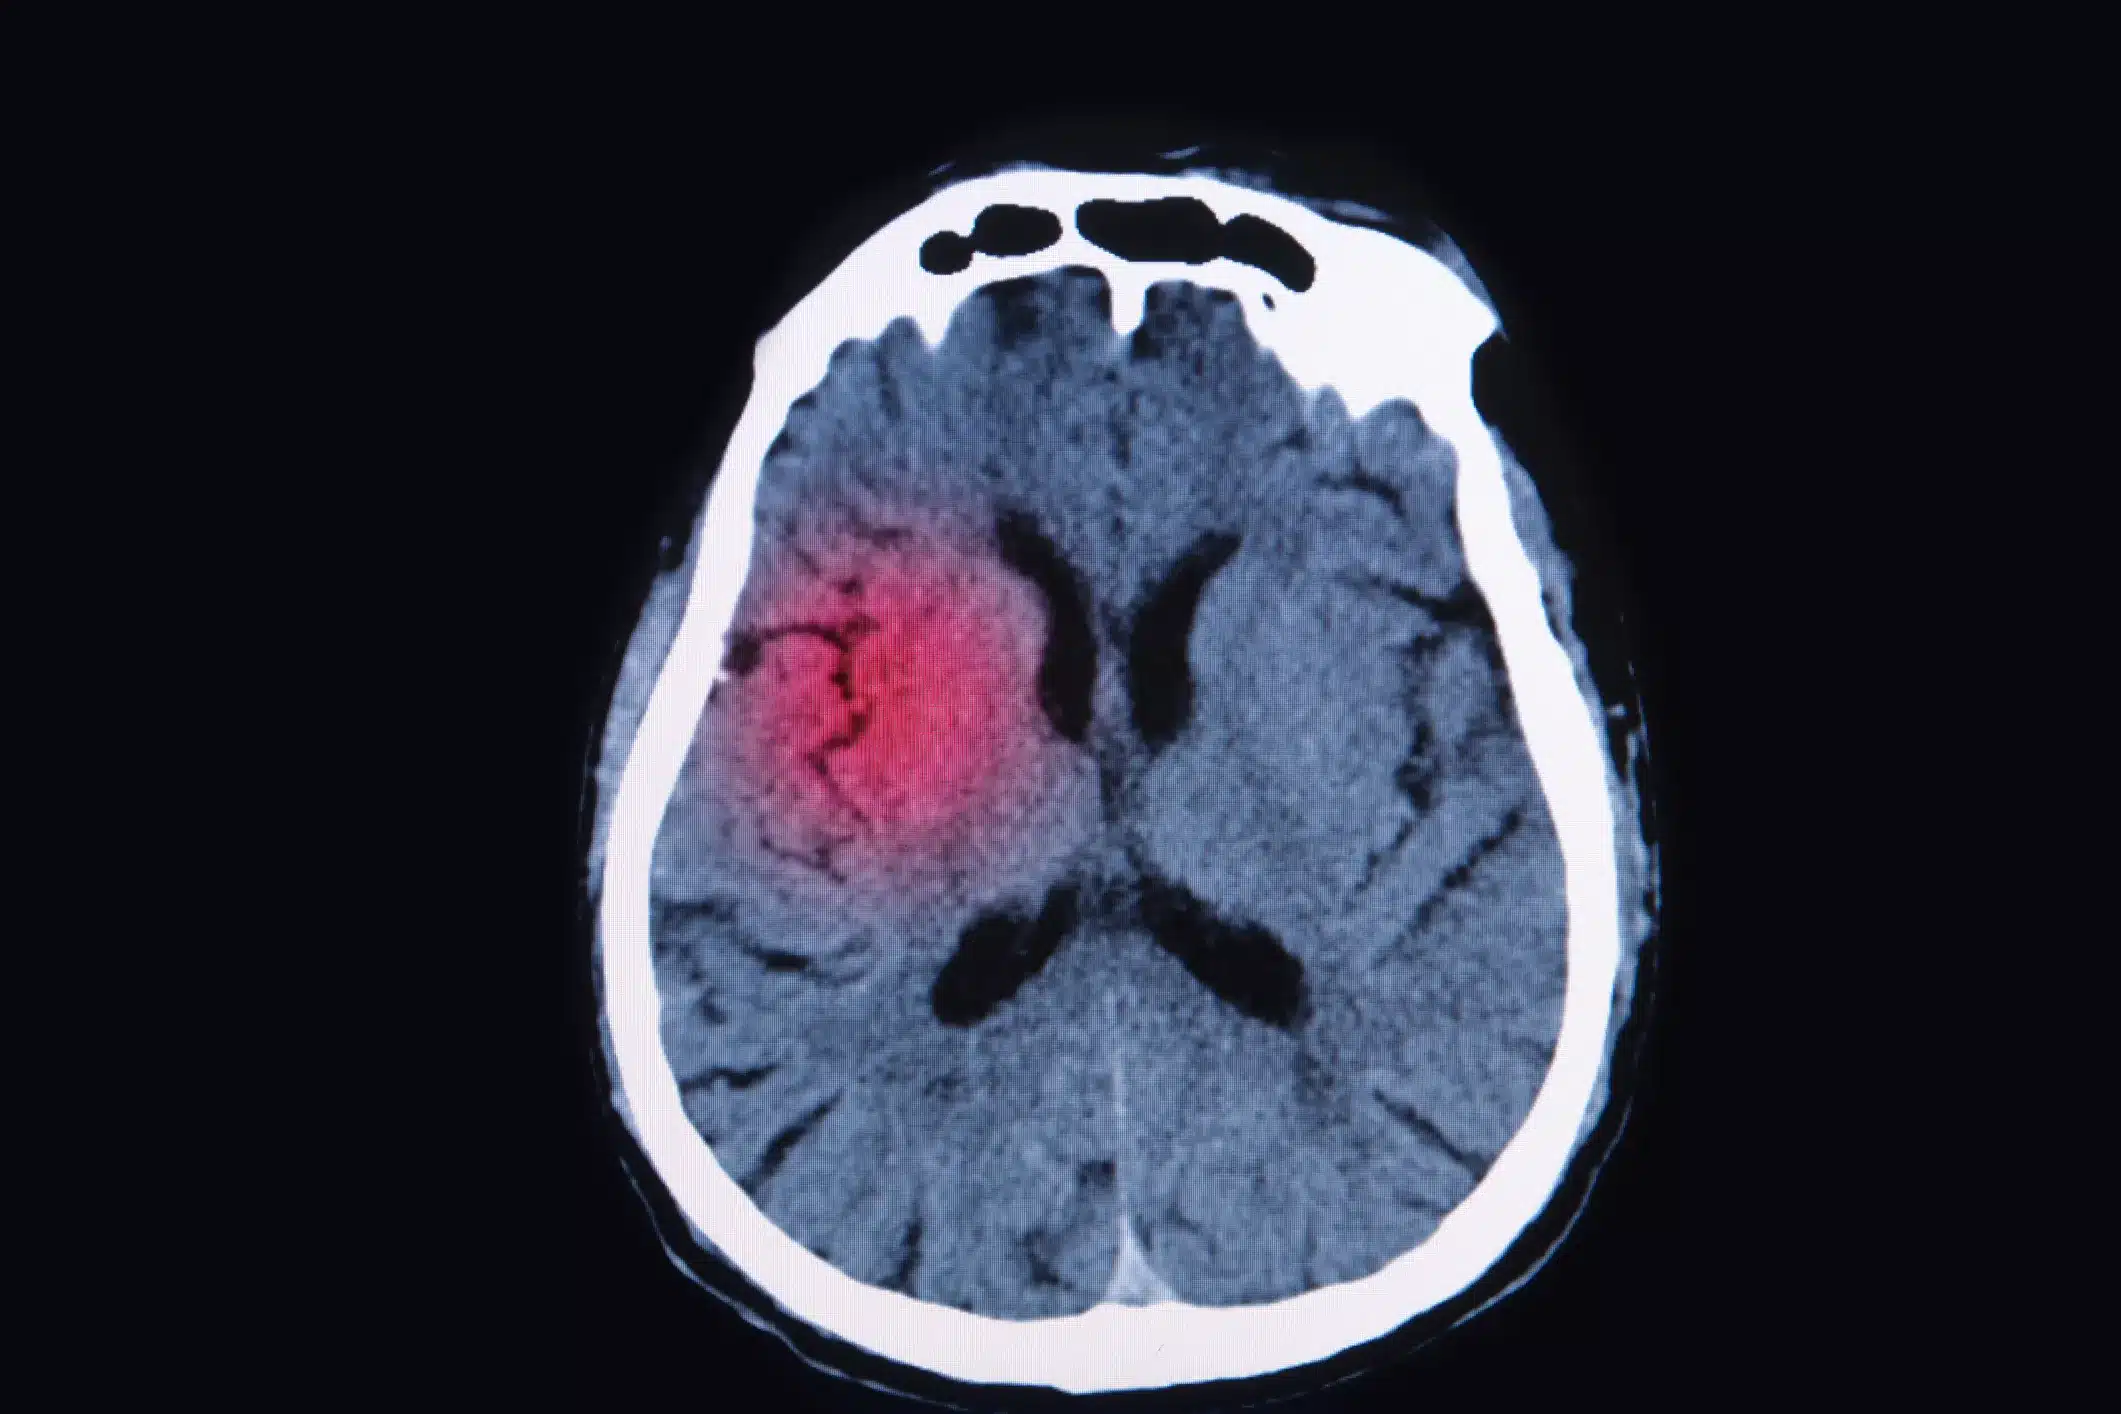

A traumatic brain injury can cause symptoms that range from mild to severe. With a mild TBI, a person can experience a headache, fatigue, or other symptoms that disappear on their own within weeks or months of onset. Comparatively, with a severe brain issue, an individual can suffer bruising, bleeding, and other long-lasting harm.